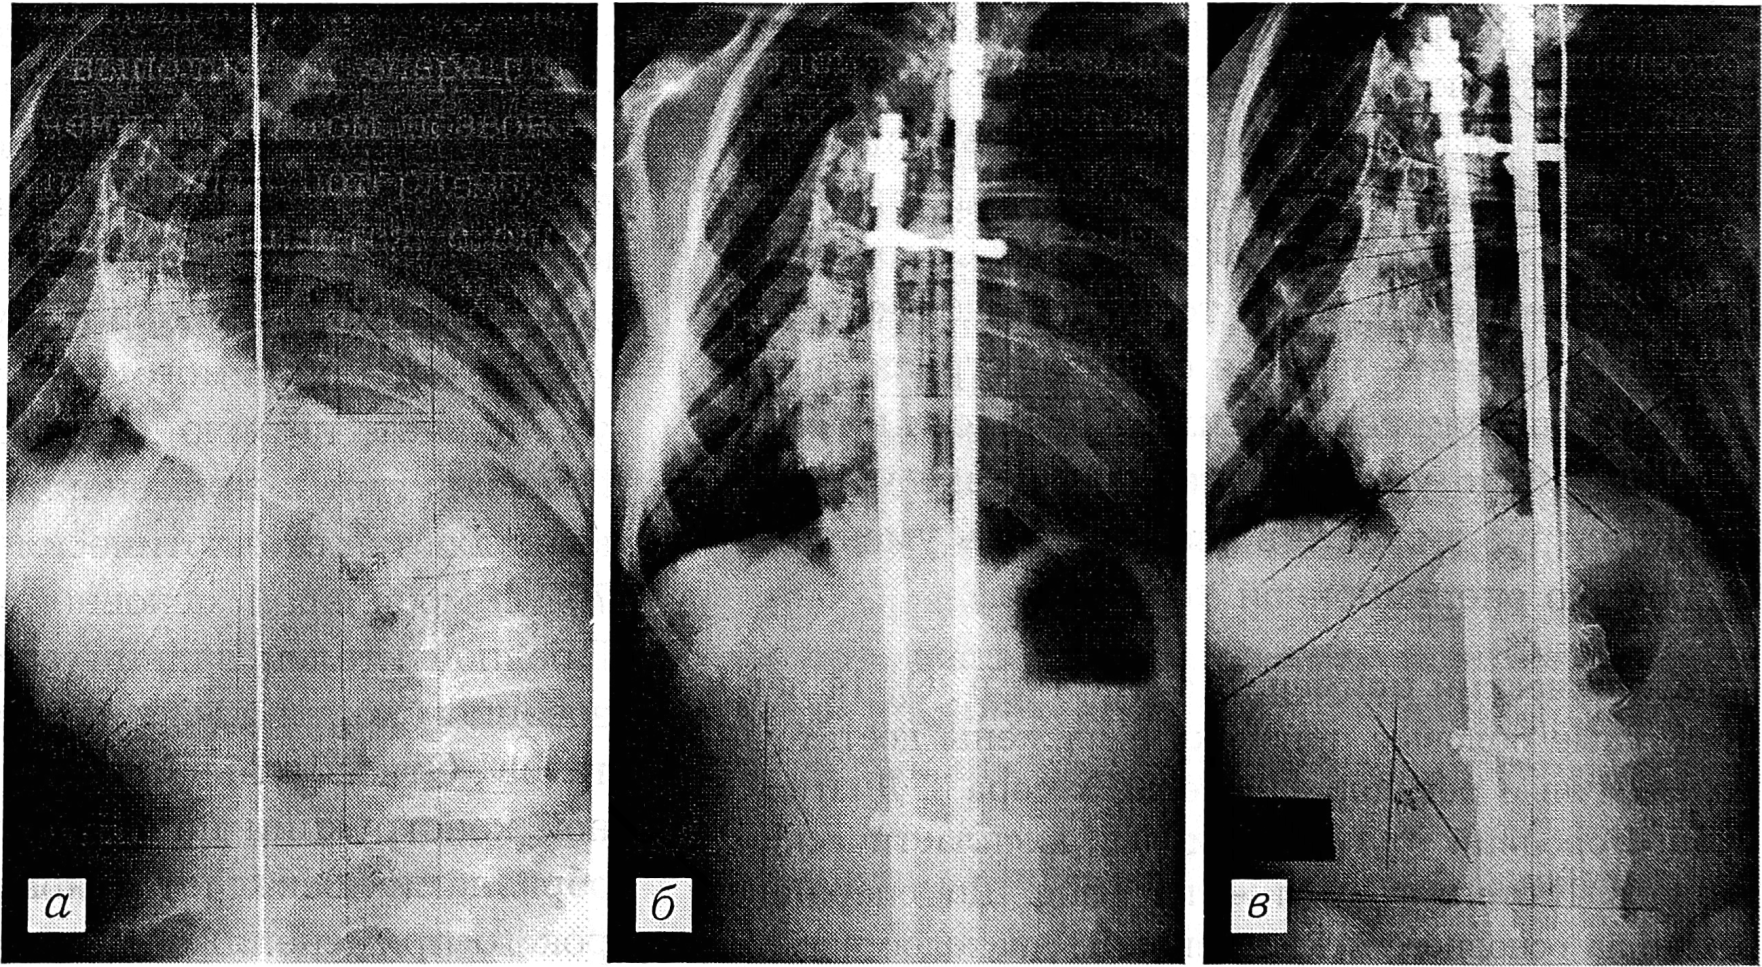

Больная С.,12 лет, диагноз: правосторонний грудной диспластический сколиоз IV степени,3 тип по King. Вторичные половые признаки выражены слабо, месячные отсутствуют, тест Риссера 0. Величина основного искривления 110°, патологическая ротация 50°, декомпенсация туловища вправо 33 мм (рис. 1, а). Произведена операция: коррекция искривления позвоночника рамочной конструкцией, задний спондилодез аллотрансплантатами. После операции величина основного искривления 62°, патологическая ротация 50°, декомпенсация туловища влево 20 мм (рис. 1, б). Через 2 года после операции величина основного искривления 88°, патологическая ротация 60°, декомпенсации туловища нет (рис. 1, в). Степень операционной коррекции основной дуги искривления 48° (48%), потеря ее 26° (54%). Патологическая ротация увеличилась на 10°.

Рис. 1. Рентгенограммы больной С. до операции (а), непосредственно после операции (б) и спустя 2 года (в).